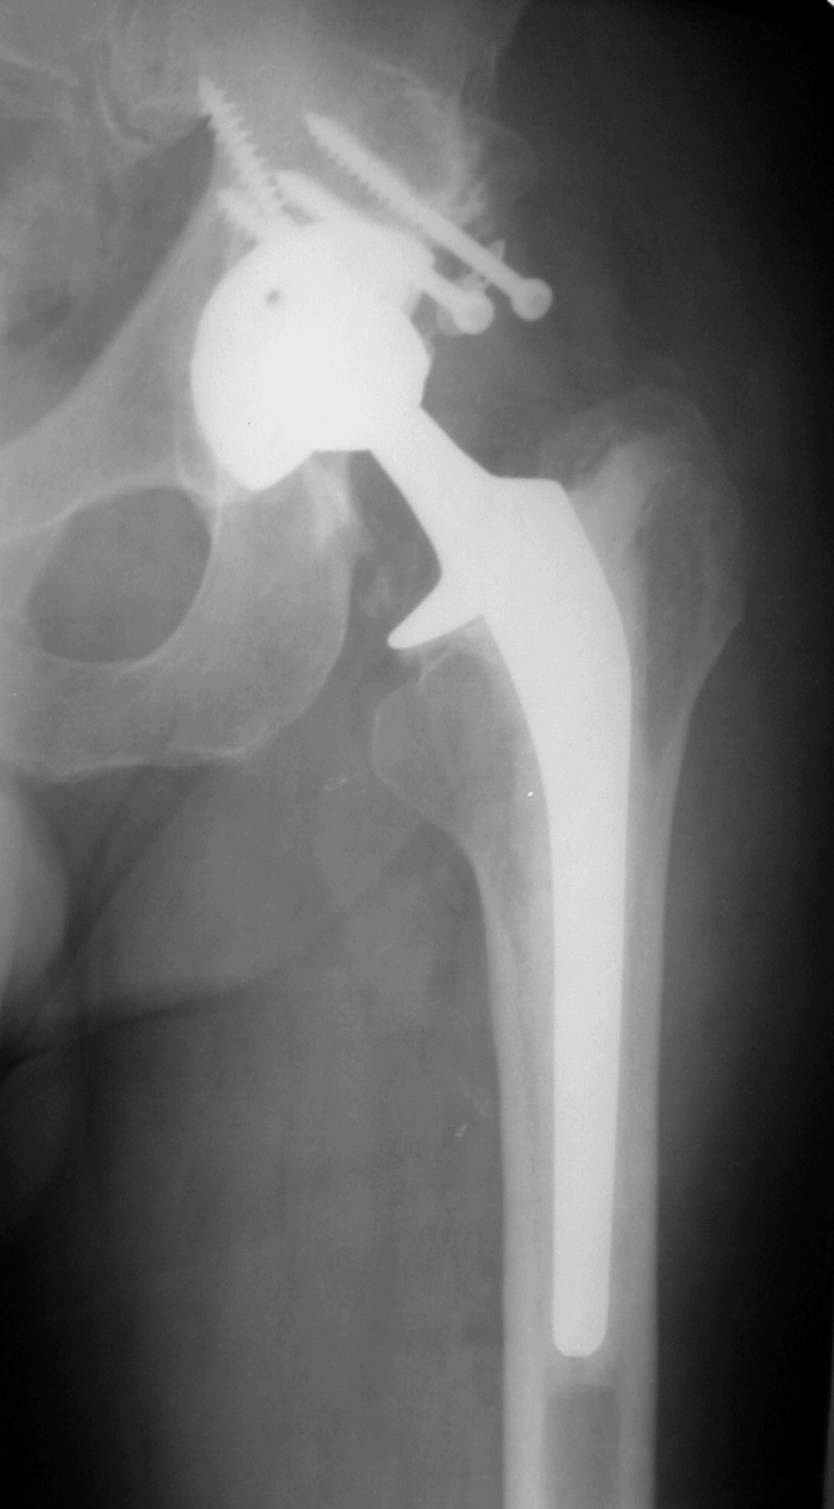

В институте совместно с фирмой Зиммер достаточно регулярно (практически ежемесячно) проводятся 2-х недельные циклы по различным вопросам эндопротезирования. Если есть возможность и желание, мы готовы поделиться с Вами нашим опытом, тем более есть что показать и что обсудить - в настоящее время ежедневно выполняется от 6 до 10 эндопротезирований коленного и тазобедренного сустава. В качестве примеров хочу показать 2 наблюдения, через 1 год и 5 лет после операции

1 год